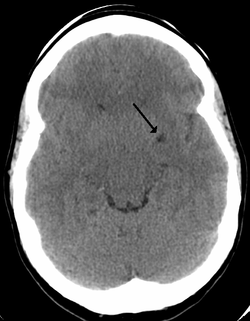

Perivascular spaces are extremely small and can usually only be seen on MRI images when dilated. While many normal brains will show a few dilated spaces, an increase in these has been shown to correlate with the incidence of several neurodegenerative diseases, making the spaces a popular topic of research.[1]

Perivascular spaces are most commonly located in the basal ganglia, thalamus, midbrain, cerebellum, hippocampus, insular cortex, the white matter of the cerebrum, and along the optic tract.[6] The ideal method used to visualize perivascular spaces is T2-weighted MRI. The MR images of other neurological disorders can be similar to those of the dilated spaces. These disorders are: [4]

Perivascular spaces are distinguished on an MRI by several key features. The spaces appear as distinct round or oval entities with a signal intensity visually equivalent to that of cerebrospinal fluid in the subarachnoid space.[4][7][8] In addition, a perivascular space has no mass effect and is located along the blood vessel around which it forms.[7]

The clinical significance of perivascular spaces comes primarily from their tendency to dilate. The importance of dilation is hypothesized to be based on changes in shape rather than size.[6] Enlarged spaces have been observed most commonly in the basal ganglia, specifically on the lenticulostriate arteries. They have also been observed along the paramedial mesencephalothalamic artery and the substantia nigra in the mesencephalon, the brain region below the insula, the dentate nucleus in the cerebellum, and the corpus callosum, as well as the brain region directly above it, the cingulate gyrus.[2] Upon the clinical application of MRI, it was shown in several studies that perivascular space dilation and lacunar strokes are the most commonly observed histological correlates of signaling abnormalities.[6]